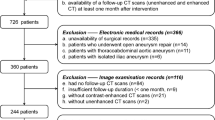

We retrospectively enrolled 378 patients who underwent non-contrast chest CT scans along with CT angiography or MRI from 4 medical centers. The training and validation sets were from 3 centers, while the external test set was from a 4th center. Radiomic features were extracted from non-contrast CT images. The radiomic signature was created on the basis of selected features by a logistic regression algorithm. The area under the curve (AUC) of the receiver operating characteristic (ROC) curve, accuracy, sensitivity, specificity, positive predictive value (PPV), and negative predictive value (NPV) were conducted to assess the predictive ability of radiomic signature.